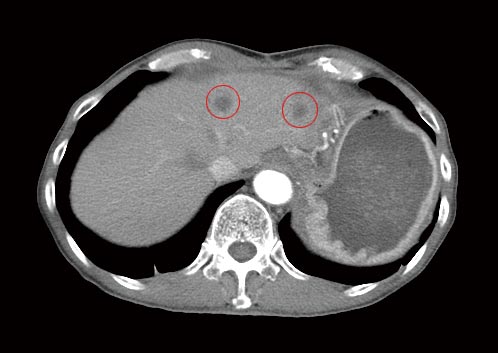

治療前のCT検査

腹部CTによって肝臓の左右(左葉と右葉)に、それぞれ直径1.5センチ程度の転移性がんが認められました。

過去に実施した手術後の再発であることを考えると、確かに根治はほとんど期待できない状況にありました。